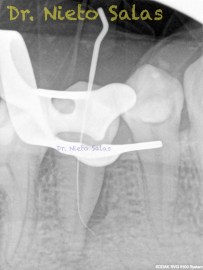

Nos llega a la clínica  este 4.5 con necrosis y periodontitis apical. la instrumentación se realizó con técnica de crown-down con limas K3 (SybronEndo) y la obturación con la técnica de ola continua de Buchanan, el tiempo de trabajo (para mi bastante importante) sobre 70-90 min.

Pero no todo se va a dejar al «poder de la irrigación»,  es muy importante la biomecánica, y la intuición para poder instrumentar esos pequeños conductos laterales que es muchas ocasiones nos dan problemas. Así, pues, os pongo un par de casos que con ayuda de esta «intuición» pudimos hacer un buen tratamiento.

Presentaban un sondaje normal, y sospechamos de que podía tratarse de lesiones por conductos laterales.

Una vez que hemos desbridado biomecánicamente con limas de muy pequeño diámetro, obturamos: